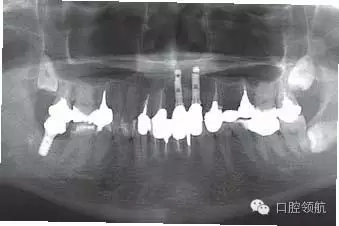

患者,53歲,男性,(右上第1、2顆牙) 缺失病例,由于牙槽骨高度不足,在行髂骨移植后進(jìn)行了種植手術(shù),但由于移植骨的吸收,種植體周圍的牙槽骨形態(tài)發(fā)生了變化引起了與對(duì)側(cè)同名牙的齦曲線明顯不對(duì)稱(圖1)。

圖1 去除愈合基臺(tái)后,由于移植骨的吸收,種植體周圍骨組織形態(tài)產(chǎn)生變化,引起與對(duì)側(cè)同名牙齦曲線明顯不對(duì)稱,作為解決的方案,提出通過外科手術(shù)再植骨和軟組織移植的方法以改善嵴頂?shù)拿缹W(xué)形態(tài)或使用修復(fù)方法來改善軟組織的美學(xué)效果。以上兩種方法供患者參考,最后患者選擇了修復(fù)的方法。